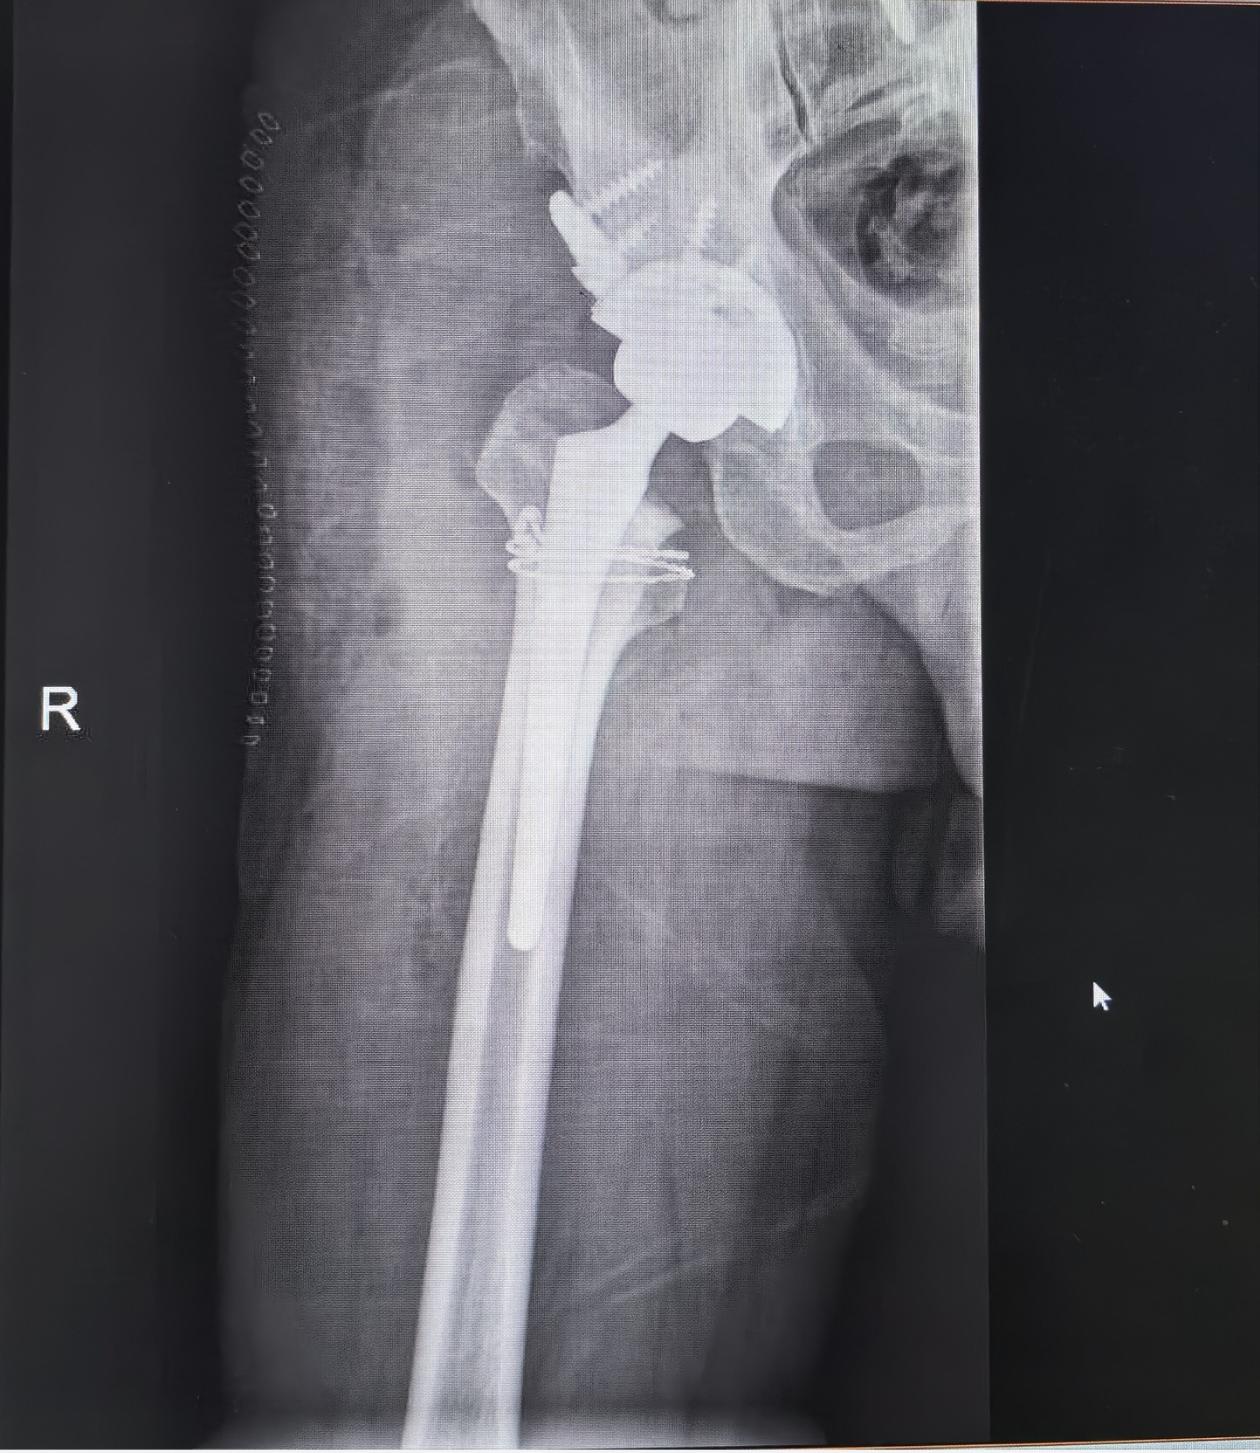

髋关节置换。1、尽量不要拖到这种程度再做手术,增加花费、创伤和手术难度;2、对于腰椎术后病人,一定要注意脊柱骨盆运动的联系,适当调整髋臼角度,否则会增加脱位和撞击风险。